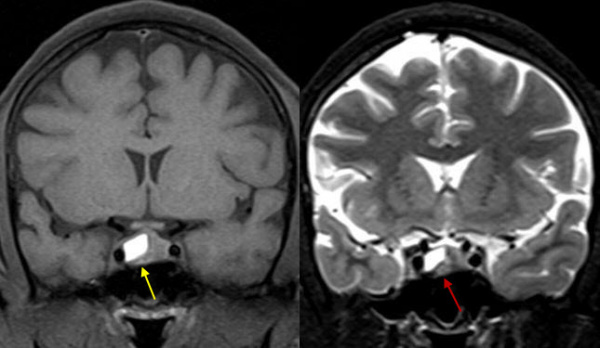

2. Больная Р., 27 лет, в 2011 г. обследована по поводу опсоменореи. Проведена МРТ гипофиза и выявлена макроаденома. После этого в течение двух лет не обследовалась и не лечилась. В январе 2013 г. возникла первая беременность. Во время беременности стала беспокоить постоянная головная боль. Проведен МРТ-контроль гипофиза (сентябрь 2013 г.), установлена отрицательная динамика: увеличение размера опухоли. Врачом женской консультации назначен каберголин по 0,25 мг 2 раза в неделю. На фоне лечения через 2 нед появились острая головная боль, тошнота, боль в глазных яблоках, резкое ухудшение общего самочувствия. Повторена МРТ гипофиза: картина — интрасупрасел-лярной макроаденомы гипофиза с признаками острого кровоизлияния. Срок беременности к этому времени составлял 36 нед. Срочно выполнено оперативное родо-разрешение; кормление грудью запрещено. Гинекологи продолжили лечение достинексом, но в меньшей дозе: по 0,125 мг 2 раза в неделю. Впервые уровень ПРЛ проверен в ноябре 2013 г.: 0,43 нг/мл (норма 5—25 нг/мл). Уровень других тропных гормонов гипофиза в норме. Доза каберголина уменьшена до 1/8 таблетки в неделю. В дальнейшем наблюдалась в поликлинике. Постепенно самочувствие стало удовлетворительным, пациентка почувствовала себя здоровой. Нормализовалась менструальная функция. Самостоятельно прекратила прием каберголина летом 2014 г. МРТ гипофиза (сентябрь 2014 г.): гипофиз расположен обычно, — сагиттальный размер составляет 1,2 см, вертикальный — справа 0,5 см, слева 0,3 см, фронтальный — 1,2 см. В центральных отделах гипофиза определяется зона гиперинтенсивного по Т1 и гипоинтенсивного по Т2 сигнала размером 0,7 х 0,4 * 0,2 см (последствия кровоизлияния?). Определяется выраженная гипертрофия хиазмы шириной до 1,4 см, толщиной до 0,8 см, умеренно деформирующая воронку. Расстояние от верхнего контура гипофиза до хиазмы 0,1 см. После введения контрастного вещества патологического изменения интенсив -ности сигнала от вещества гипофиза не выявлено. Пациентка жалоб не предъявляет. Нормализовалась менструальная функция. Уровень тропных гормонов, в том числе ПРЛ (13,08 нг/мл), в норме, глазное дно и поля зрения в норме. По медицинским документам и результатам МРТ пациентка проконсультирована в Институте нейрохирургии им. Н.Н. Бурденко проф. Б.А. Кадашевым: полная резорбция макроаденомы гипофиза после перенесенного кровоизлияния в опухоль. Наблюдение продолжается, отрицательной динамики нет.